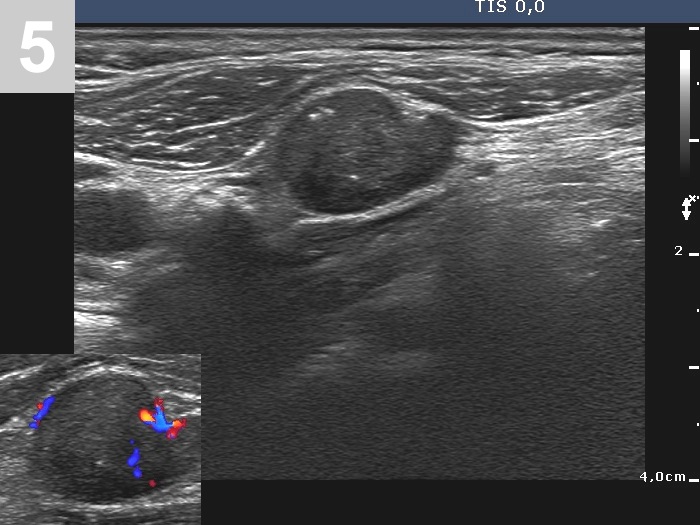

3 US of thyroid cancer

Pre- and postoperative ultrasound in thyroid cancers

Cases to be discussed on January 18, 2024